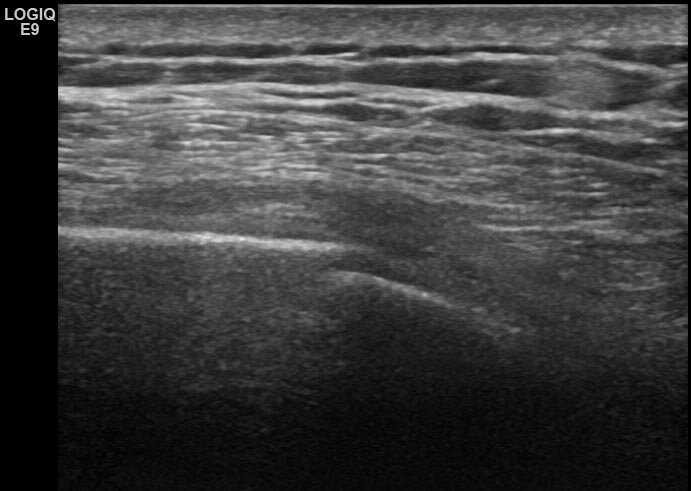

На скользкой дороге пациент упал на спину, появилась боль в пояснице. Обратился для ультразвукового исследования почек. При ультразвуковом исследовании почки без травматических изменений. при досмотре линейным датчиком (15 МГц) определяется прерыв кортикального слоя 12 ребра (сканирование по лопаточной линии, параллельно ходу ребра) с небольшим боковым и угловым смещением. Отмечается параоссальная гематома. Видео к наблюдению: https://dzen.ru/video/watch/66596ded09ad8755b3d03139?rid=1780210364.371.1717137121425.73442&t=1

При ультразвуковом исследовании почки без травматических изменений. при досмотре линейным датчиком (15 МГц) определяется прерыв кортикального слоя 12 ребра (сканирование по лопаточной линии, параллельно ходу ребра) с небольшим боковым и угловым смещением. Отмечается параоссальная гематома.